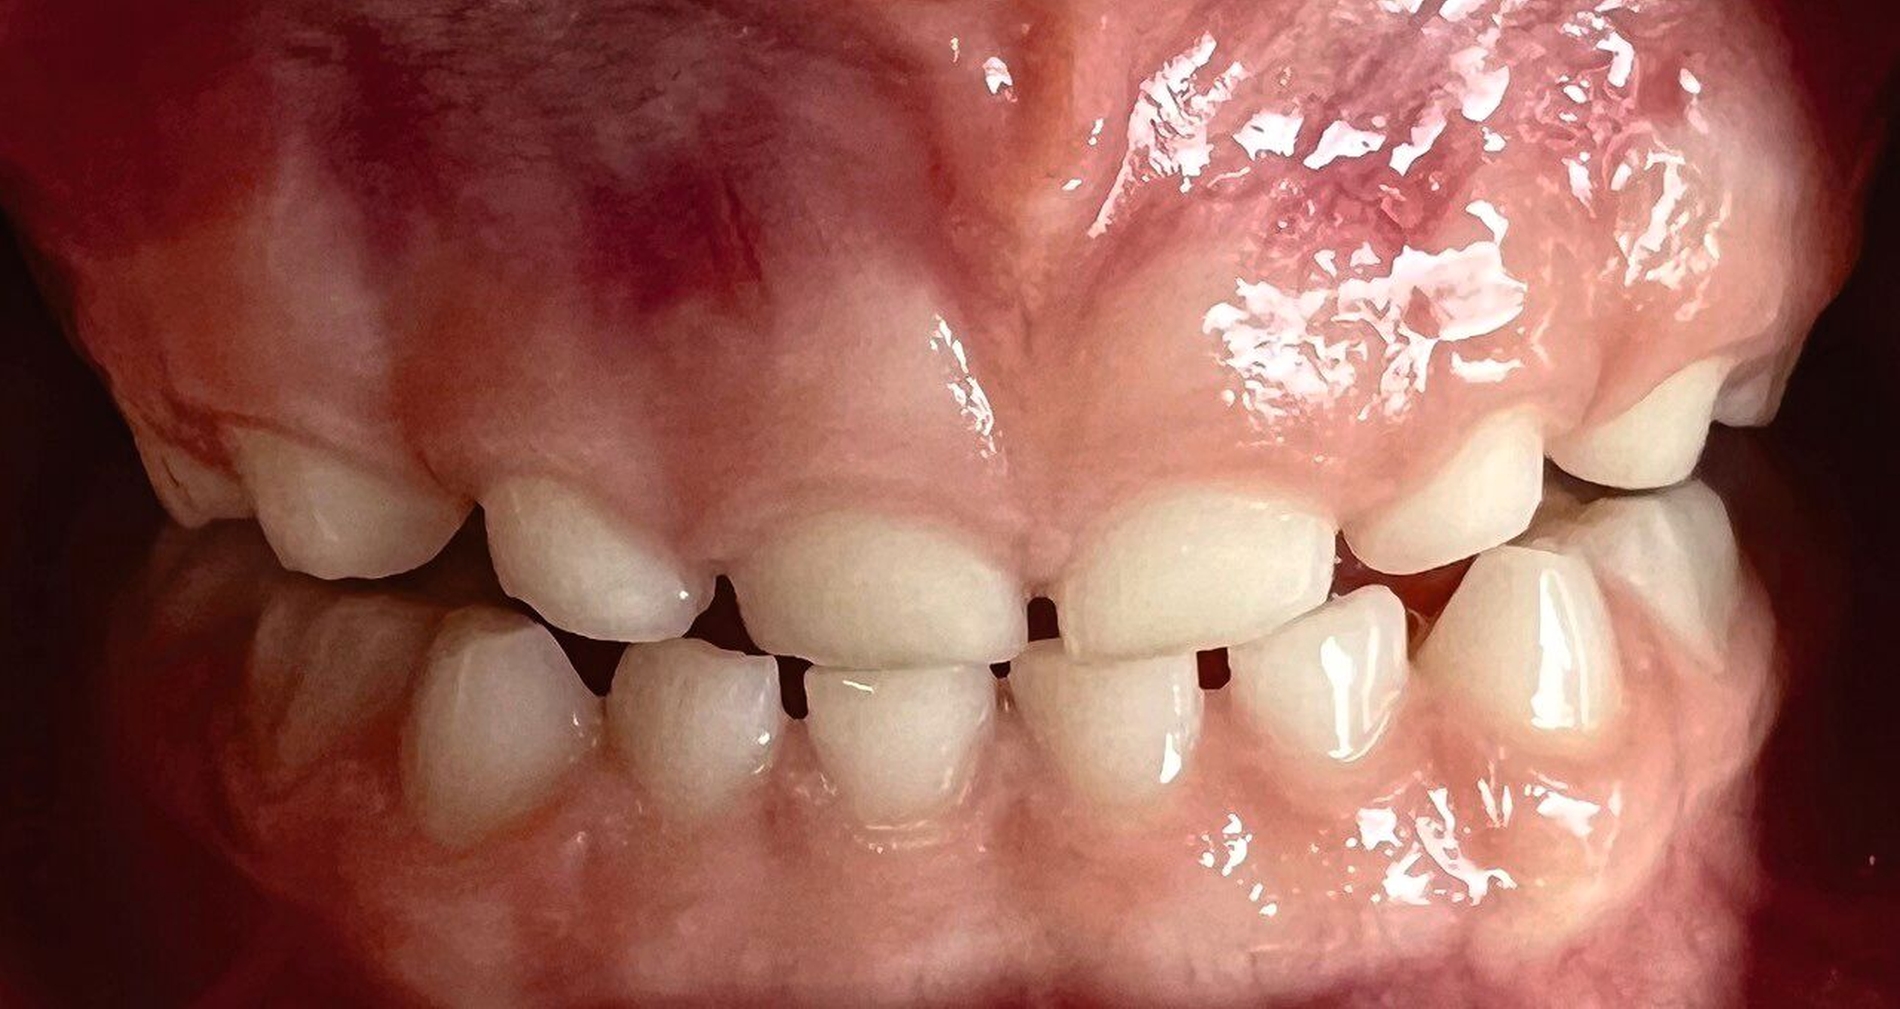

Wenn der Patient nach dem Schlafen über Beschwerden in der Kaumuskulatur oder Beeinträchtigungen im täglichen Leben klagt, handelt es sich um eine schwerwiegende statische Form. Über die Beurteilung der Schlifffacetten an den Front- und Seitenzähnen wird die Diagnose der dynamischen Form erhoben. Diese kann entweder an Studienmodellen oder direkt im Mund erfolgen. Der Schweregrad der Attritionen reicht von der alleinigen Schmelz- bis zur Pulpabeteiligung. Schließlich muss man Zahnhartsubstanzverlust, der bis ins Dentin reicht, bei Kindern und Jugendlichen als schwere Form des Bruxismus bewerten, da die Zähne vergleichsweise kurz in der Mundhöhle sind (Abbildungen 3 und 4).

Nicht zuletzt können auch morphologische Gegebenheiten eine ausschlaggebende Rolle in Bezug auf Bruxismus spielen. So können gewisse Zahn- und Kieferfehlstellungen Attritionen fördern, wie dies zum Beispiel beim Kopf- oder Deckbiss der Fall ist (Abbildung 5), während andererseits große vertikale Abweichungen oder sagittale Stufen selten zu klinischen Bruxismuszeichen führen, weil die Zähne nicht in Okklusion stehen. Dies ist meist recht einfach zu diagnostizieren.